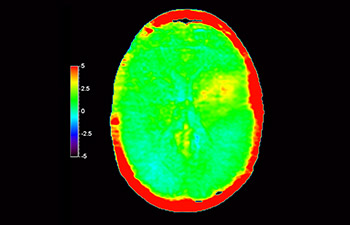

Rezidivierendes Glioblastom

Aufnahme des Gehirns zur Untersuchung auf ein rezidivierendes Glioblastom

mit 3D APT